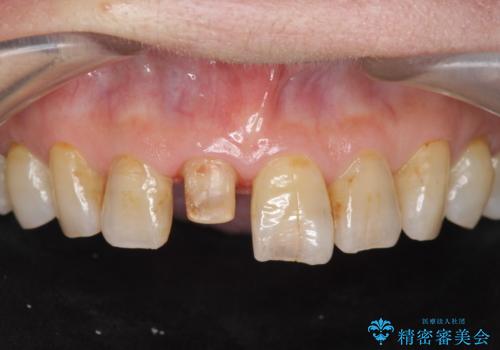

- 前歯を転倒で受傷し、審美性の回復を求めて来院されました。

近医で暫間的なコンポジットレジン修復が為されていましたが、色調に不満があるということでした。

色調の変化が少なく、長期的な予後を見込めるジルコニアクラウンで天然歯を模した審美性の回復を計画します。